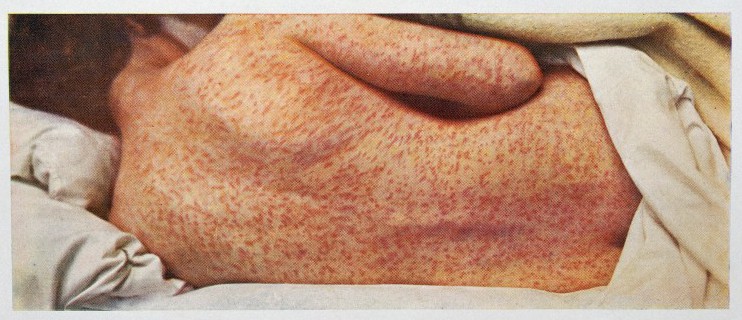

Measles

World Health Organization on measles

World Health Organization on measles- Kids’ Health on measles

- Virus, respiratory droplets, highly contagious

- Symptoms: fever (over 104), cough, runny nose, conjunctivitis (red eyes), red flat rash starting on the face, and spreading down the body.

- Complications: common complications such as ear infections and diarrhea, to severe complications of pneumonia or encephalitis.

- Death/statistics: 1 in 20 children develop pneumonia, 1 in 1000 children develop encephalitis, swelling of the brain that can cause seizures, deafness or mental retardation if it is survived.

- In the U.S., before vaccination in 1963, there were 3 to 4 million cases of measles each year. Of those people, 400 to 500 died, 48,000 were hospitalized, and 4,000 developed encephalitis.

- Worldwide, in 2013, there were 145,700 deaths.

- “400 deaths a day, 16 deaths an hour.”

- Before widespread vaccination, measles caused an estimated 2.6 million deaths each year.

- Measles was considered eliminated from the United States in 2000. That is, there were no transmitted cases between residents of the US.

- One dose of measles vaccine is about 93% effective, and two doses are about 97% effective.